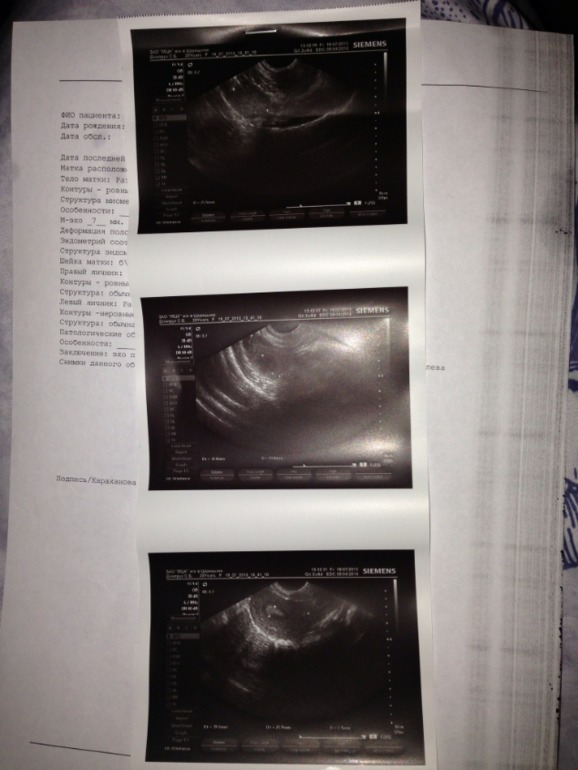

А что именно не понятного? Эндометрий соответствует 2 фазе, доминантный фолик есть. Хронический аднексит это воспаление хроническое

Чо такое доминантный фолик?Хронический аднексит? Почему врач ничего не сказал? Как это лечить? Чем грозит? Откуда????А по тому что вы видите, на Б есть надежда в этом цикле???(Переехала к мужу, пошла в платную ЖК, ужасное отношение в ней... Очень переживаю. Что у врача не спрошу-ни одного четкого ответа)